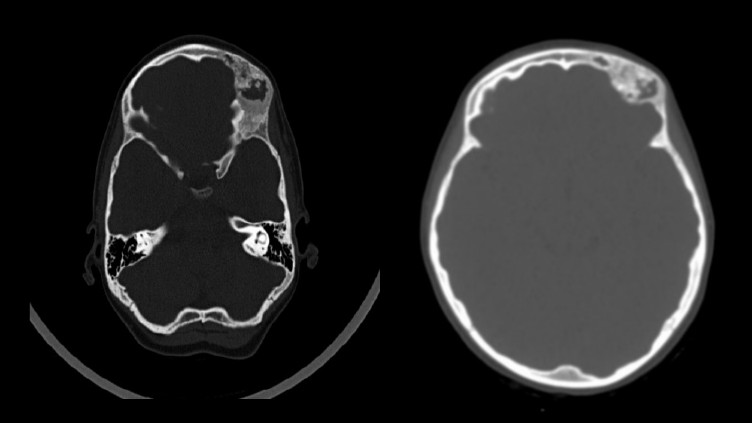

A 17‑year-old male had a multi-slice computed tomography MSCT scan due to asymmetry observation in his forehead on the end of September 2023 which raised suspicions of a pathological formation. Upon consultation at RCCH at the beginning of July 2024, the patient was admitted in to the maxillofacial surgery department for further treatment and observation.

Diagnosis

The MSCT imaging revealed edema, deformity structure exhibits uneven compaction resembling a “ground glass” appearance in the right frontal bone (Figure 5). A diagnosis of fibrous dysplasia of the right frontal bone was established.

Additionally, a preoperative three-dimensional image and axial computed tomographic scan illustrate the distinctive ground-glass opacification characteristic of fibrous dysplasia affecting the left frontal, temporal, and sphenoid bones.

Fig. 5. A preoperative coronal computed tomographic image obtained on September 2023, reveals dysplastic growth of the left temporal bone, which is associated with frontal involvement and displacement of the orbital contents

A 6 years old boy has been ill since 2016, when a forehead asymmetry was first noticed by his parents. After one month later, a CT scan was performed and a bone density formation was found in the area of the zygomatic arch of the frontal bone and in the area of the parietal bone on the left (Figure 8). The patient was admitted to the maxillofacial surgery department for treatment in RCCH on 2016 after consultation.

MSCT of the skull shows the affected osseous which is related to polyostotic craniofacial form of fibrous dysplasia in the left frontal bone and left parietal bone (25×40 mm in size and 7 mm in thickness). Locally, a bone density formation is visualized and palpated in these areas, originating from the bones (Figure 9).

Fig. 9. Preoperative axial CT image exhibiting characteristic homogeneously dense appearance of fibrous dysplasia involving the left frontal bone